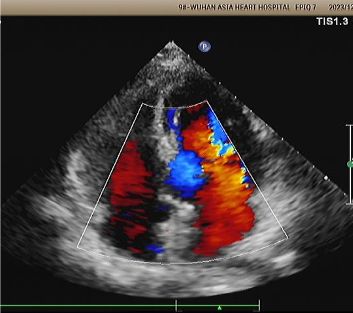

Implant: 2424 memosorb®Eko ve dsa rehberliği altında konuşlandırılan biyobozunur pfo occluder.

Gün 1 ila 9 ay:

Artık şant gözlenmedi.